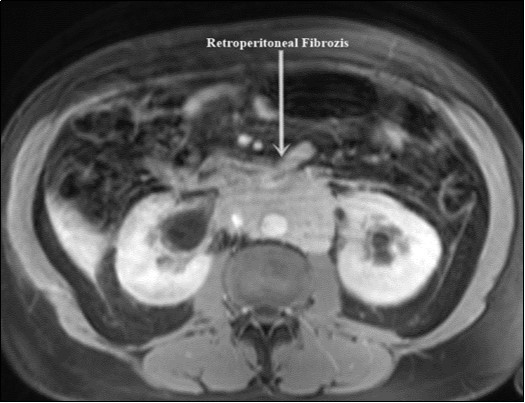

A 58-year-old male patient was admitted to our clinic with complaints of severe weakness, loss of appetite and decreased urine volume. The patient had chronic, mild lower urinary tract symptoms. Serum creatinine level of the patient was 5.3 mg/dl and he had no additional diseases except hypertension. Bilateral grade 3 hydronephrosis and moderate residual urine was revealed in urinary ultrasonography. A transurethral foley catheter was inserted and the patient was admitted to the internal medicine intensive care unit with the diagnosis of acute renal failure due to infravesical obstruction. During follow-up, abdominal magnetic resonance imaging (MRI) was performed due to oliguria and high serum creatinine level (Figure 1). Magnetic resonance imaging revealed a mass of approximately 88x49 mm in the axial plane at the renal artery outlet level, consistent with retroperitoneal fibrosis, tuberculous lymphadenitis or lymphoma. Grade 3 pelvicaliectasis was seen in bilateral kidneys. The descripted lesion was observed in paraaortic area (except posterior). Tru-cut biopsy was planned with no evidence of malignancy on positron emission tomography. Tru-cut biopsy reported as connective tissue. Bilateral double-J ureteral stent was placed endoscopically to patient who was diagnosed as idiopathic retroperitoneal fibrosis (Figure 2). At the same time, alpha-blocker treatment was started. Creatinine levels decreased to normal after five days and normal volume voiding was observed after removal of foley catheter. The patient was started on glucocorticoid therapy which was foreseen to last for 1 year. After 2 months, PET imaging showed the decreased mass size and metabolic activity. Thereafter bilateral ureteral double-J stents were removed endoscopically. Ultrasonographic imaging showed no hydronephrosis after 7 days of catheter removal and the patient was recommended to continue glucocorticoid therapy and was followed up.

Figure 1.Retroperitoneal fibrosis involving both ureters.